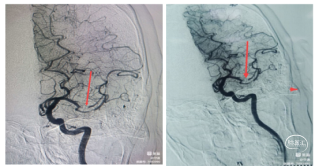

右侧颈总造影发现,右侧颈内动脉起始处有斑块,两处充盈缺损。

使用泥鳅导丝试探,很幸运,毫不费劲就通过了狭窄处,因此考虑此处未完全闭塞,而且远处的栓子可能就来源于此处。将5F125cm Navien沿着泥鳅导丝轻松通过狭窄处,进行抽吸清理颈内动脉可能滞留血栓。跟进8F导引导管通过狭窄部位起到支撑作用。

上干和大脑前为功能区血管,应该开通:

先开通大脑中M2段。支架导管到位,确认远端通畅,尼科医疗的Reco支架3X20mm到位,5F Navien跟到M1,一边抽吸一边拉栓,一把拉通。

再开通大脑前A2段,同样尼科医疗的Reco支架3X20mm到位,5F Navien 跟进A1,半收拢支架,一边抽吸一边拉栓,一把拉通。

回头处理颈内动脉起始部。常规保护伞4-6mm保护下行4-6mm球囊扩张,并自膨支架7-9-40mm植入。